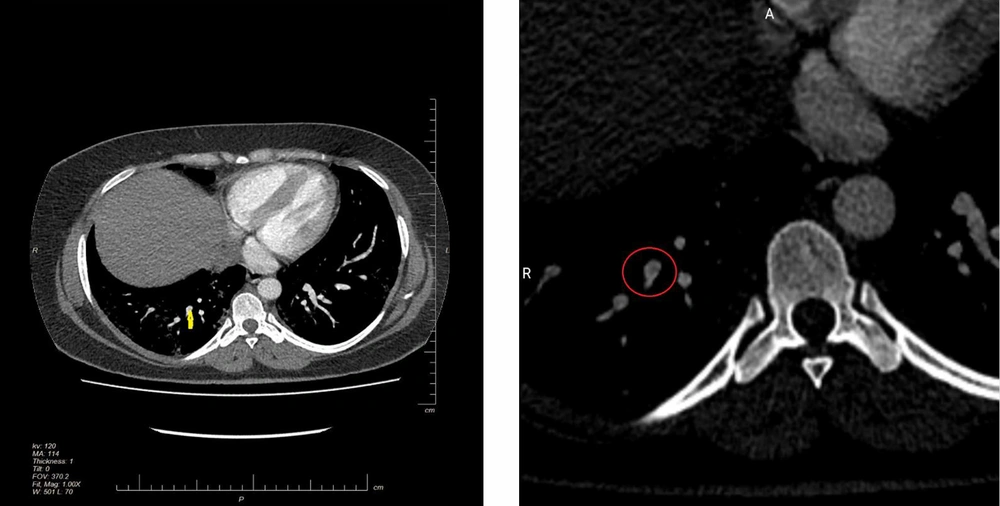

On the second day of admission, the patient developed hemoptysis and had greater breathing difficulties. Additionally, the blood oxygen saturation had become 82 percent in ambient air, and the patient was receiving oxygen by a mask with a reservoir bag. A consultation was made with the gynecologic and internal medicine wards in regard to next treatment steps. We performed a biophysical profile for the fetus and obtained a score of 10 out of 10. The patient was put on intravenous immunoglobulin by an internist doctor. On the second day of admission, the patient deteriorated at nighttime, and oxygen saturation remained below 82 percent amid oxygen therapy with 7 liters of oxygen provided via mask with a 2-liter reservoir. At this point, we proceeded with an emergency Cesarean section. The patient was then admitted into an intensive care unit (ICU). The patient complained of heartbeat palpitation and mild discomfort in her chest. An ECG showed an S wave in the lead I, q wave in lead II and sinus tachycardia, suggestive of right ventricle straining. The patient had a transthoracic echocardiography, which showed an ejection fraction of 45% - 50%. Severe right ventricle enlargement was also evident, with moderate to severe dysfunction of the right ventricle. A consultation with the Cardiology Department suggested further investigation to rule out pulmonary embolism. The patient was immediately put on low molecular weight heparin, and a CT pulmonary angiography was performed. The results illustrated filling defects and confirmed the diagnosis of pulmonary thromboembolism. The patient was then re-admitted to the ICU where treatment was continued. On the second day of ICU admission, the patient had oliguria for more than 12 hours; a consultation conducted with the Nephrology Department suggested that hemoperfusion should be performed. Following the hemoperfusion procedure, the patient was stabilized. The findings of the imaging studies are presented in Figures 1 and 2, with the clinical course of the patient presented in Figure 3.